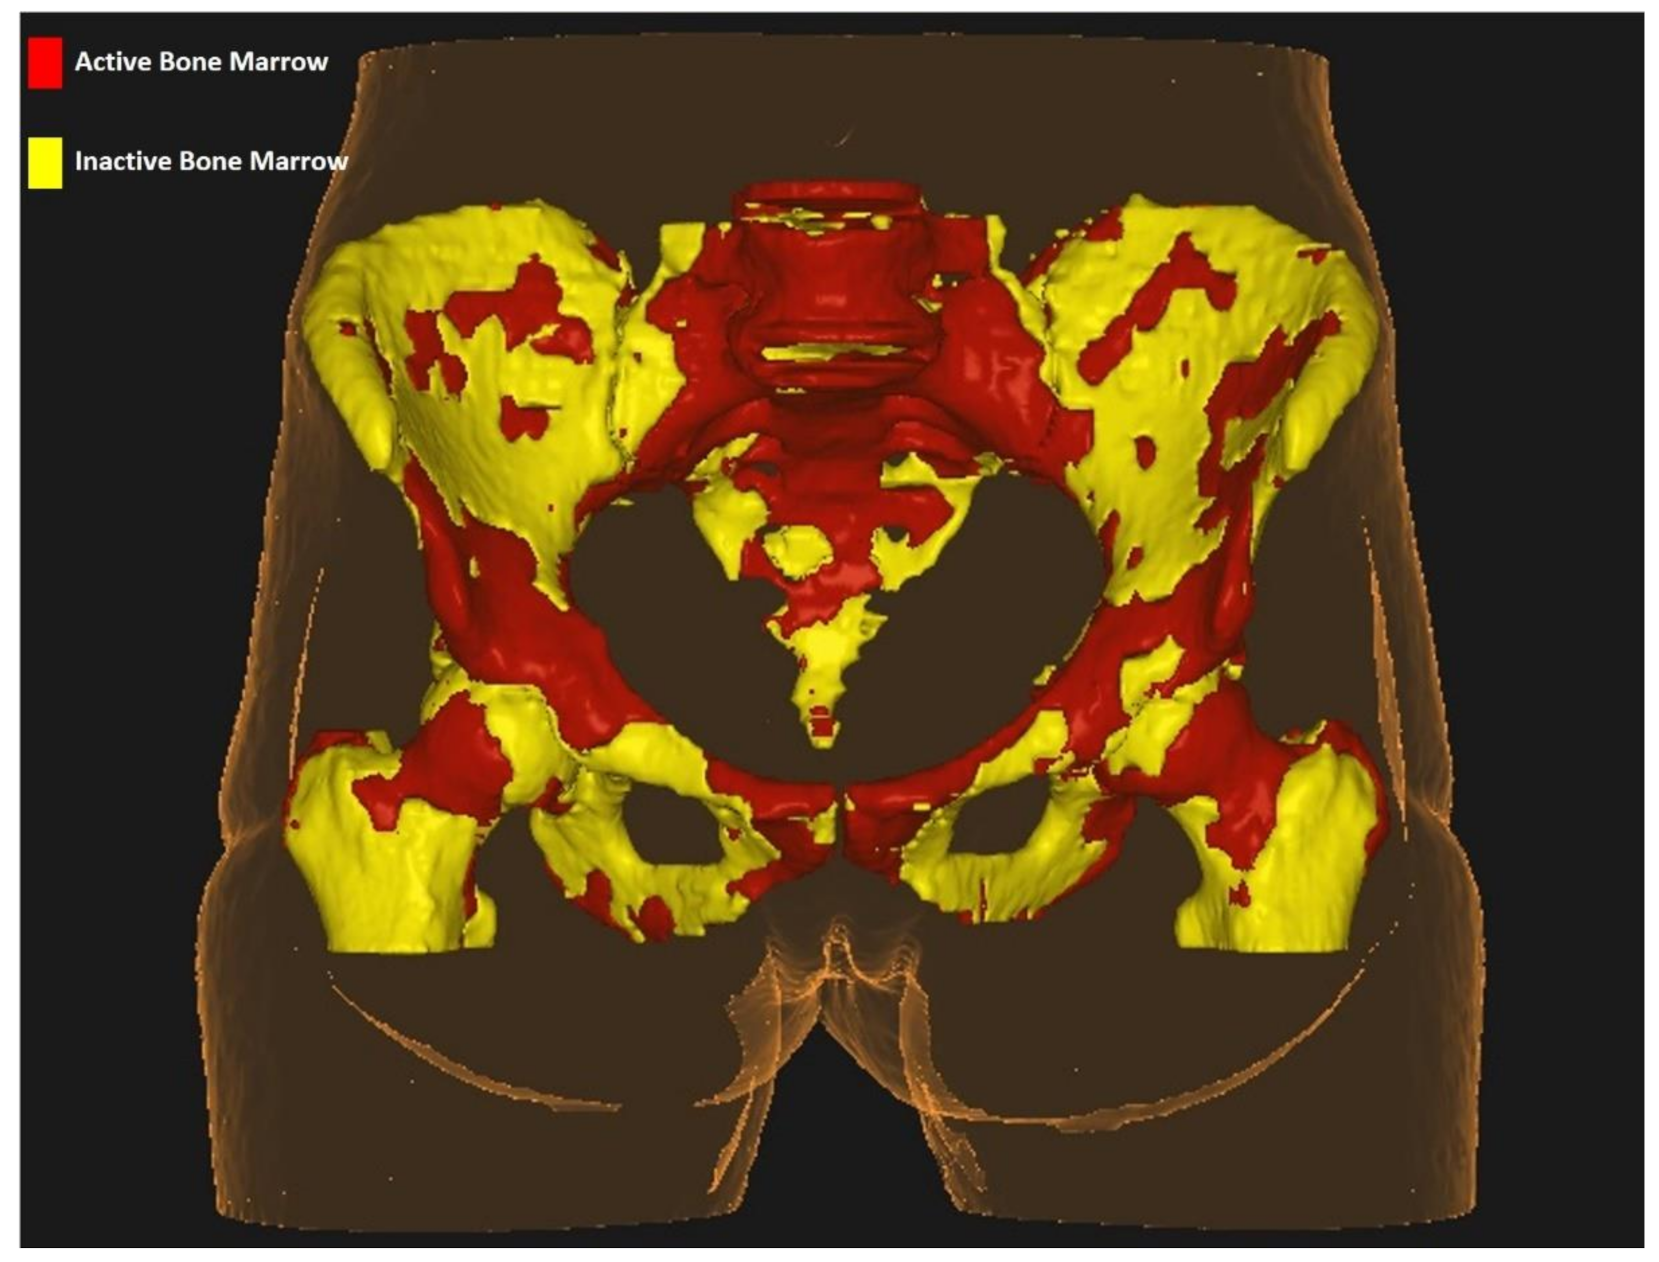

2.5. Active Bone Marrow Delineation on 18FDG-PET

All images derived from planning computed tomography were exported on the Velocity platform (Varian Medical Systems, Palo Alto, CA, USA) together with treatment volumes, organs at risk, and dose references. Given that 18FDG-PET images were acquired separately, we performed a rigid co-registration between computed tomography and 18FDG-PET. Moreover, 18FDG-PET standardized uptake values (SUVs) were calculated for PBM volumes, after correcting for body weight. To standardize SUVs among all patients, we normalized BM and liver SUVs. We defined as active bone marrow (ACTBM), the volume with higher SUV values than the SUVmean for each patient, rather than the whole cohort, as proposed by Rose et al. [11]. The areas identified with the method described above were outlined within PBM as a whole and named ACTBM and within each of the 3 subregions identified on planning computed tomography (LSBM, IBM, LPBM) and named ACTLSBM, ACTIBM, ACTLPBM, respectively. Inactive BM (INACTBM) was identified as the difference between BM volumes as defined on planning computed tomography (PBM) and ACTBM. The same procedure was repeated for all 3 subregions to identify inactive BM within all of them. The 3 volumes were hence called INACTLSBM, INACTIBM, INACTLPBM. Figure 1 highlights ACTBM (red) and INACTBM as identified with the use of 18FDG-PET in a specific patient included in the study.

Figure 1. Active bone marrow segmentation within the pelvis.